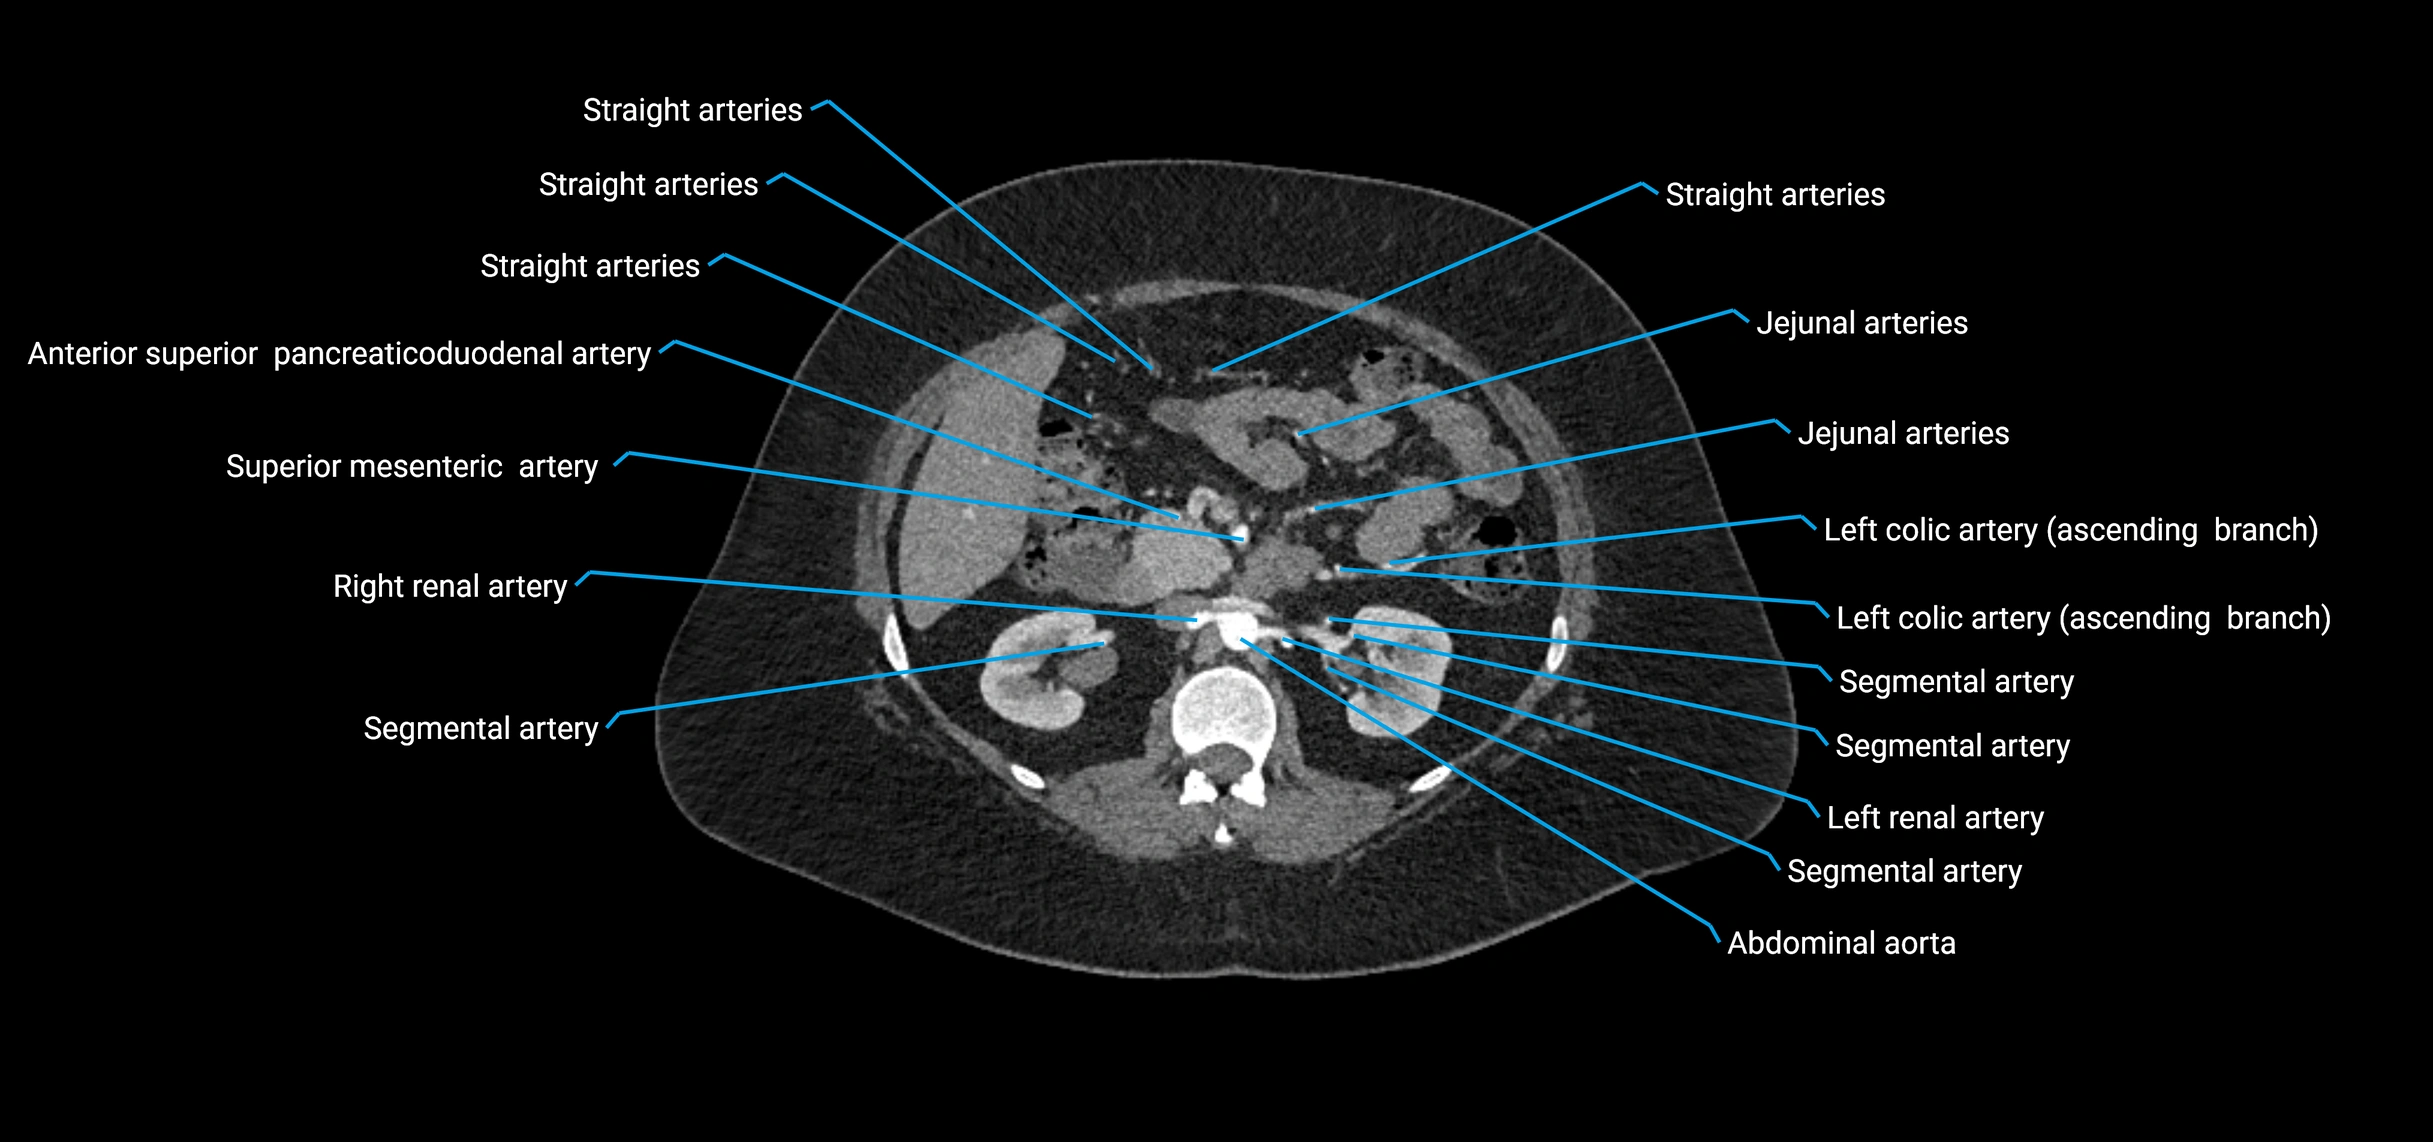

Contrast-enhanced CT (CTA):

• Gold standard for abdominal aortic imaging

• Provides excellent detail of lumen, wall, aneurysm, thrombus, and branch vessels

• Multiplanar and 3D reconstructions help in aneurysm measurement, stent graft planning, and dissection evaluation

• Detects acute rupture, traumatic injury, or occlusion with high sensitivity